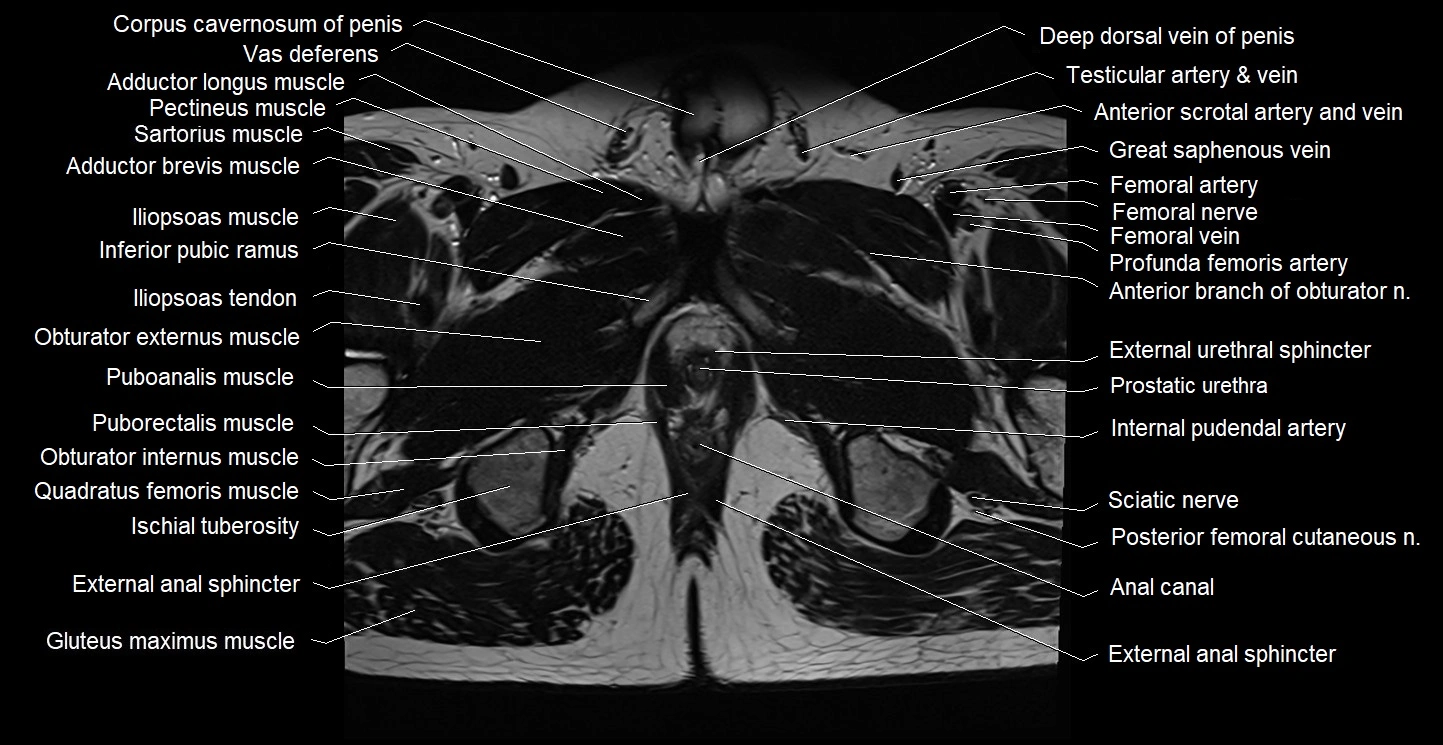

- Anal canal

- Deep dorsal vein of penis

- External anal sphincter

- External urethral sphincter (male)

- Femoral artery

- Femoral nerve

- Femoral vein

- Gluteus maximus muscle

- Iliopsoas muscle

- Iliopsoas tendon

- Inferior pubic ramus

- Internal anal sphincter

- Internal pudendal artery

- Ischial tuberosity

- Levator ani muscle

- Obturator externus muscle

- Obturator internus muscle

- Pectineus muscle

- Posterior femoral cutaneous nerve

- Prostatic urethra

- Puboanalis muscle

- Puborectalis muscle

- Quadratus femoris muscle

- Sartorius muscle

- Sciatic nerve

- Vas deferens